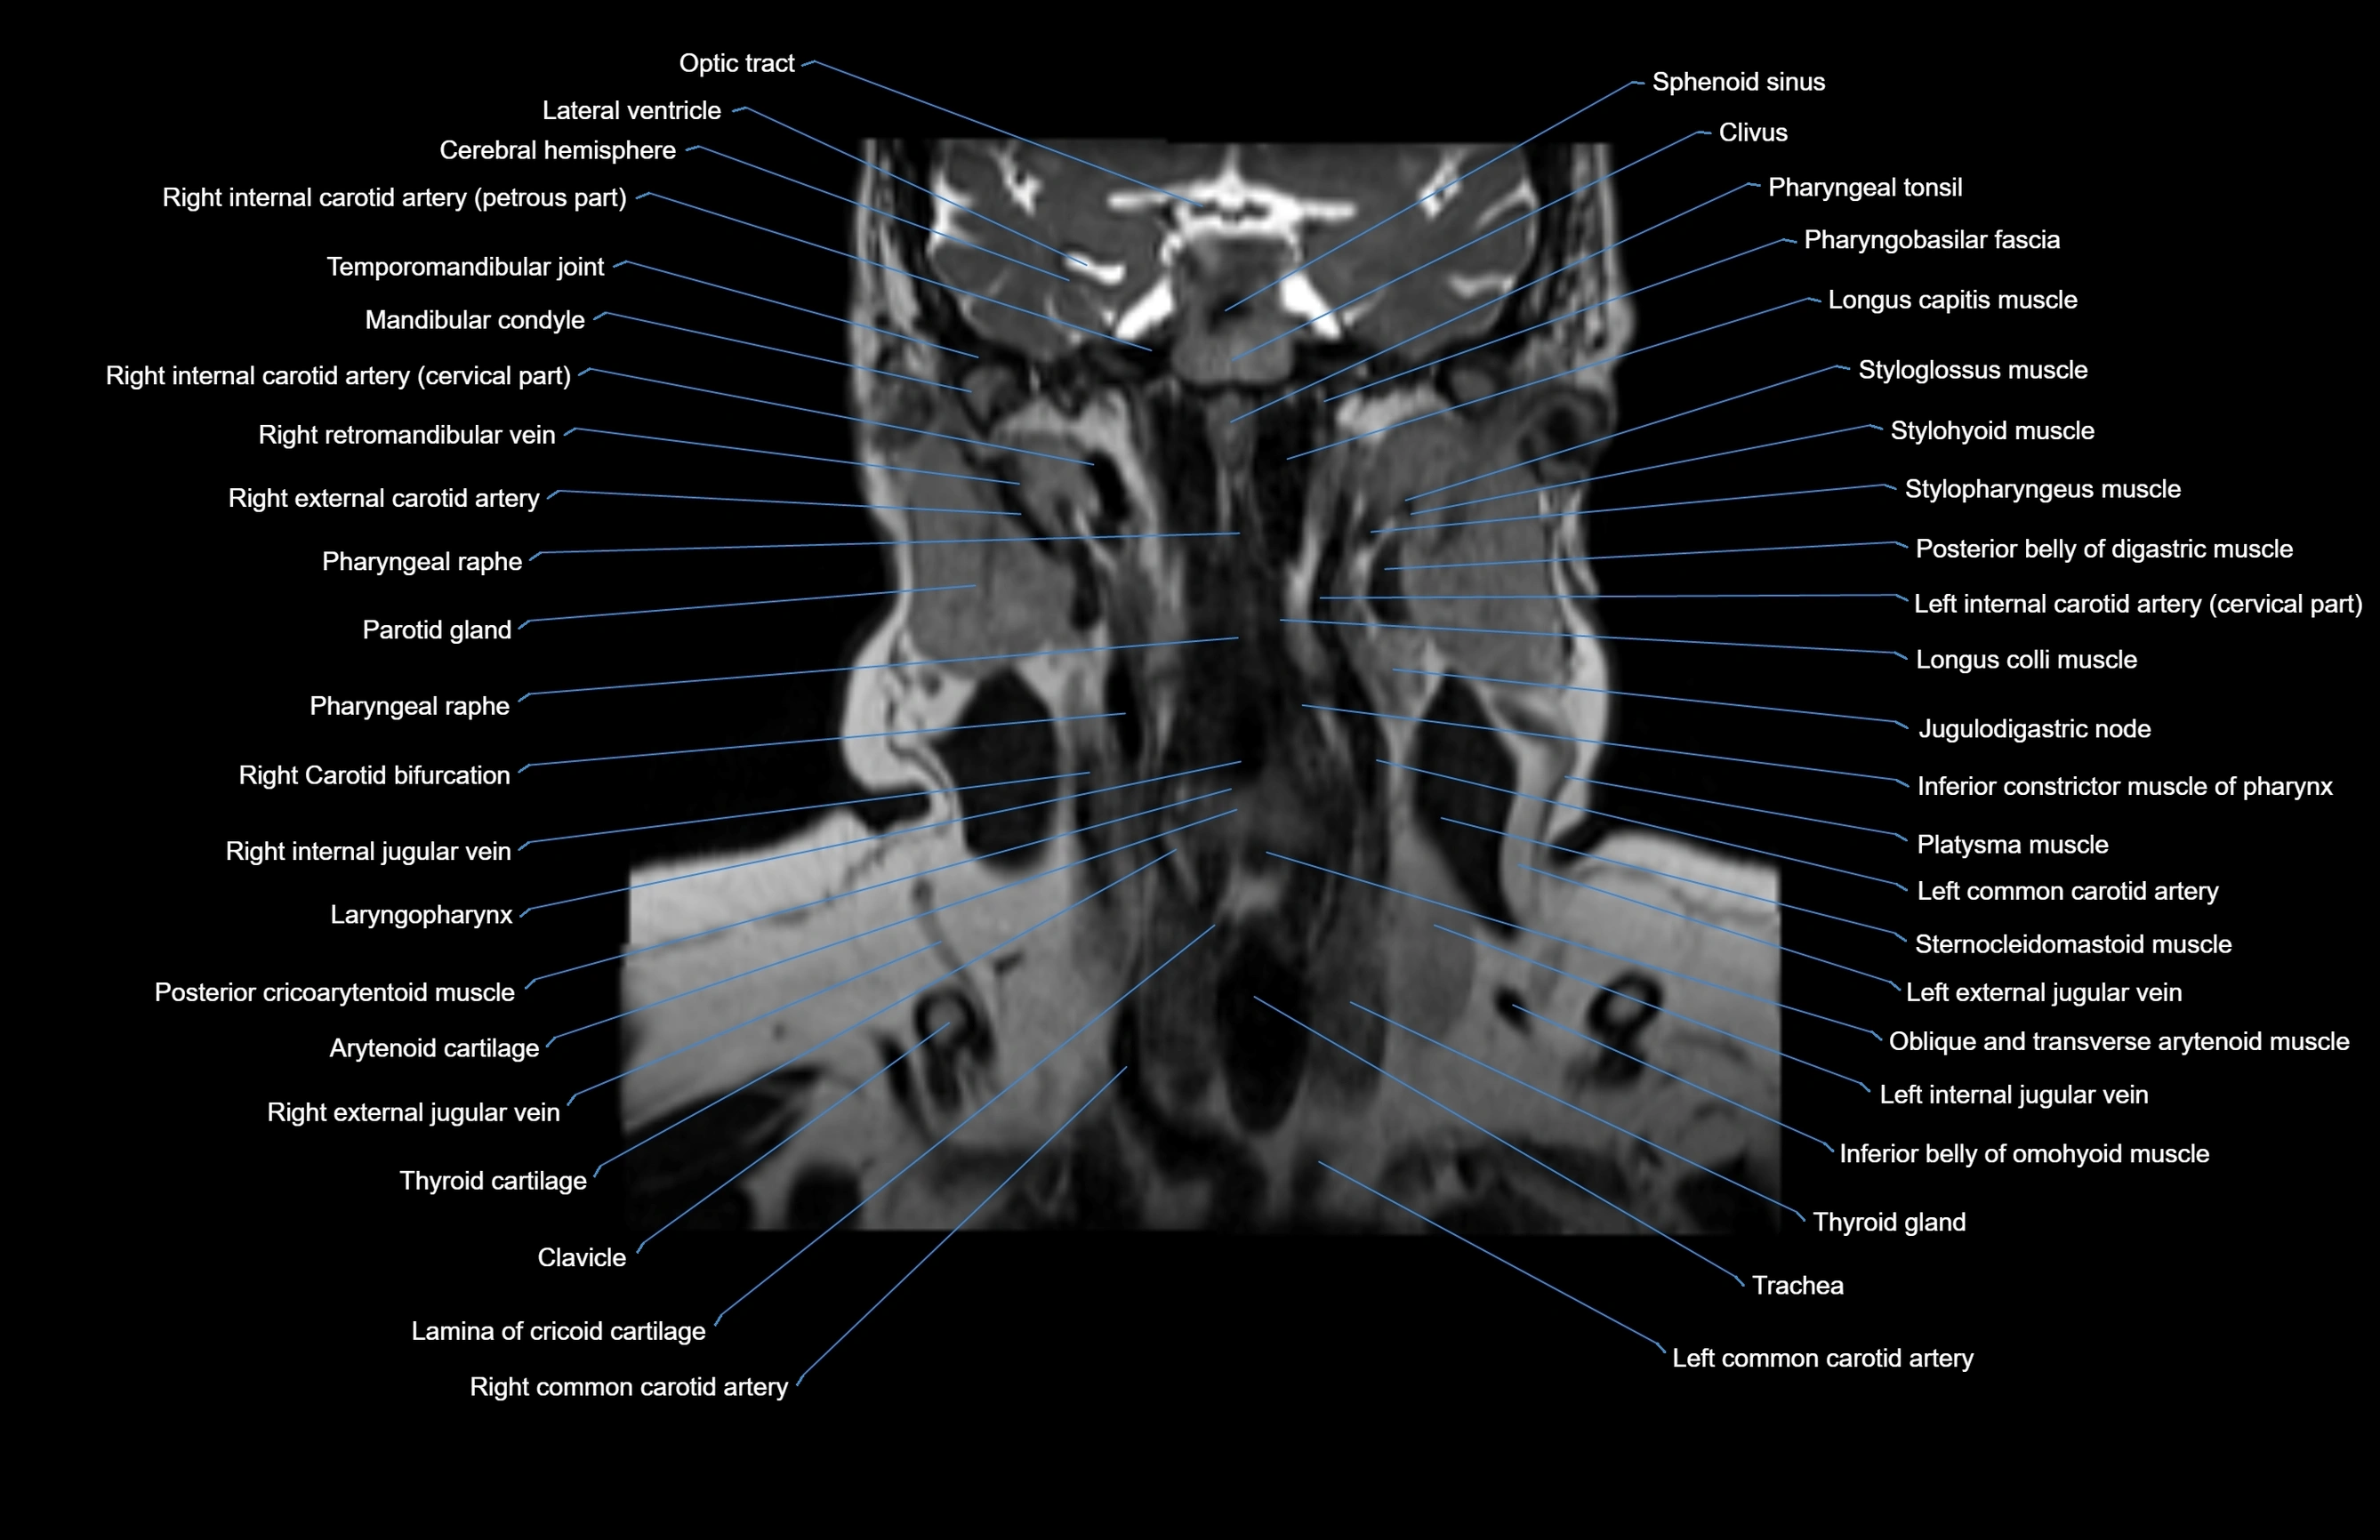

MRI images